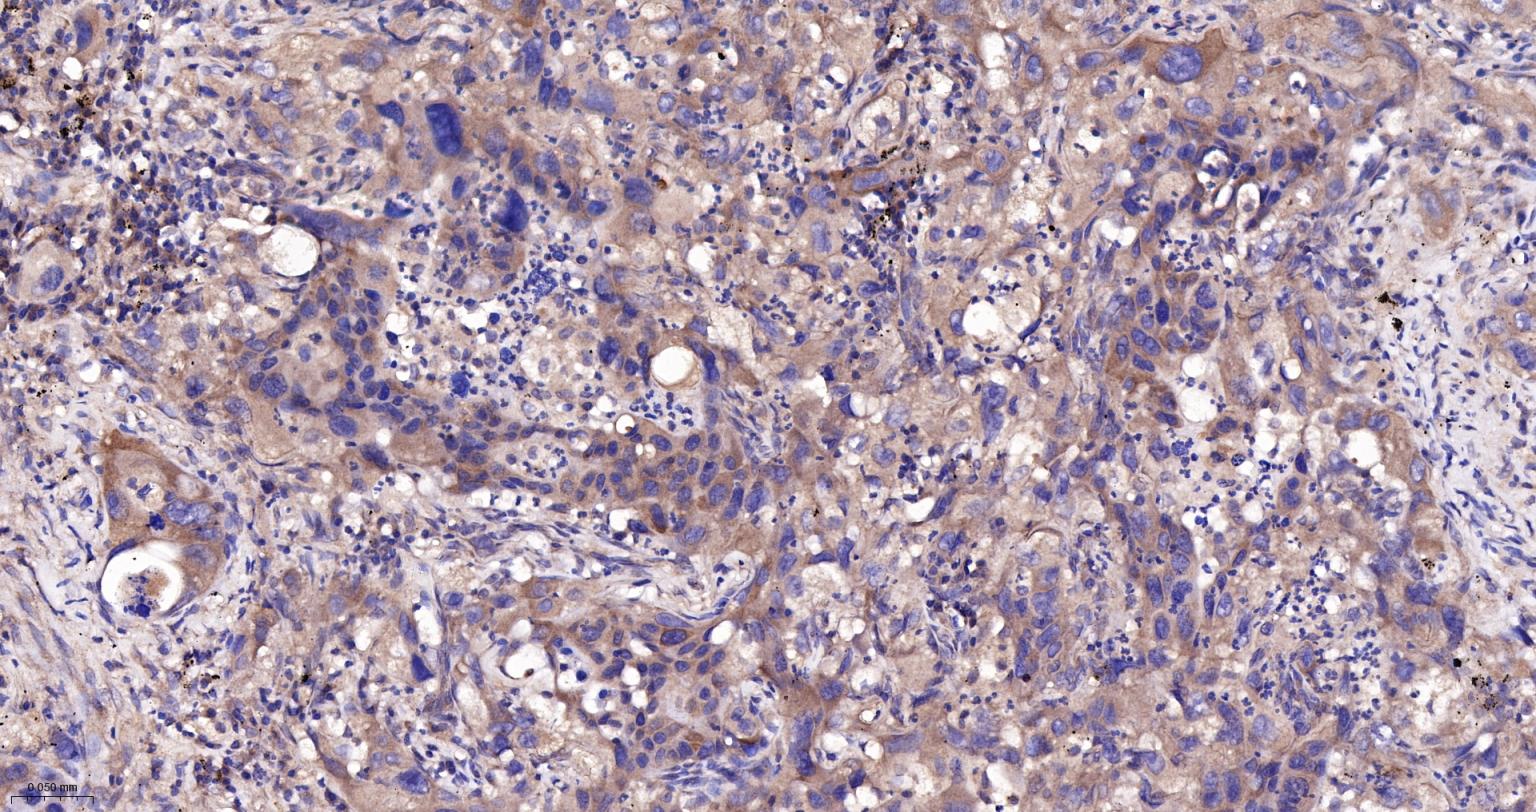

Paraformaldehyde-fixed, paraffin embedded Human Gastric Cancer; Antigen retrieval by boiling in sodium citrate buffer (pH6.0) for 15 min; The section was incubated with Ubiquitin D Monoclonal Antibody, Unconjugated (bsm-61330R) at 1:200 overnight at 4°C, followed by conjugation to the bs-0295G-HRP and DAB (C-0010) staining.

Paraformaldehyde-fixed, paraffin embedded Human Lung Cancer; Antigen retrieval by boiling in sodium citrate buffer (pH6.0) for 15 min; The section was incubated with Ubiquitin D Monoclonal Antibody, Unconjugated (bsm-61330R) at 1:200 overnight at 4°C, followed by conjugation to the bs-0295G-HRP and DAB (C-0010) staining.